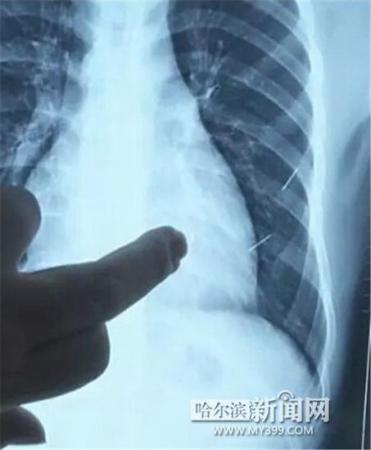

醫(yī)生指出X光片上的針狀物

昨日上午,記者在哈醫(yī)大二院第八住院部心外三病房找到了躺在病床上痛苦不堪的董立仁,家屬正在他身旁不斷安慰著他。見記者前來,董立仁母親李百燕拿出一張X光片,上面可以清晰地看到胸腔內(nèi)一共有4根針狀物,其中一根在心臟部位,兩根在胸腔壁上,還有一根在腹腔壁上。

心外三病房董立仁的主治醫(yī)生告訴記者,董立仁送到醫(yī)院時(shí)病情很危險(xiǎn),隨時(shí)可能危及生命?!巴ㄟ^檢查發(fā)現(xiàn),他心臟內(nèi)有一個(gè)金屬異物,正好在心臟上。心臟每次跳動(dòng)都與其產(chǎn)生摩擦,導(dǎo)致出血,心包積液懷疑是血液。如果大量出血會(huì)凝結(jié)成血塊,血塊包裹住心臟就會(huì)影響心臟跳動(dòng),隨時(shí)都有停跳的危險(xiǎn)。心臟上的異物是致命傷,其余胸腔壁和腹腔壁的異物傷害不大?!?/p>

昨天16時(shí)30分左右取針手術(shù)開始。因鋼針隨時(shí)會(huì)危及患者生命,此次手術(shù)定義為大型手術(shù)。開胸后,醫(yī)生打開董立仁心包,發(fā)現(xiàn)一枚鋼針已深深扎入心臟,僅露出1厘米長(zhǎng)度在外。拔出鋼針后,醫(yī)生發(fā)現(xiàn),這枚針長(zhǎng)達(dá)5厘米。受鋼針影響,心包出現(xiàn)大量積液,近800毫升。

隨后,在下胸壁位置,第二枚鋼針順利取出。在尋找另兩枚鋼針過程中,普外、胸外多名醫(yī)生也參與手術(shù),為主刀醫(yī)生提供更為穩(wěn)妥的處理建議。根據(jù)X光片顯示位置,醫(yī)生未在患者體內(nèi)找到剩余兩枚鋼針。醫(yī)生懷疑,其中一枚鋼針可能深藏在肋骨骨膜位置,無法尋找,最后決定結(jié)束手術(shù),做進(jìn)一步觀察,研究下一次手術(shù)方案。